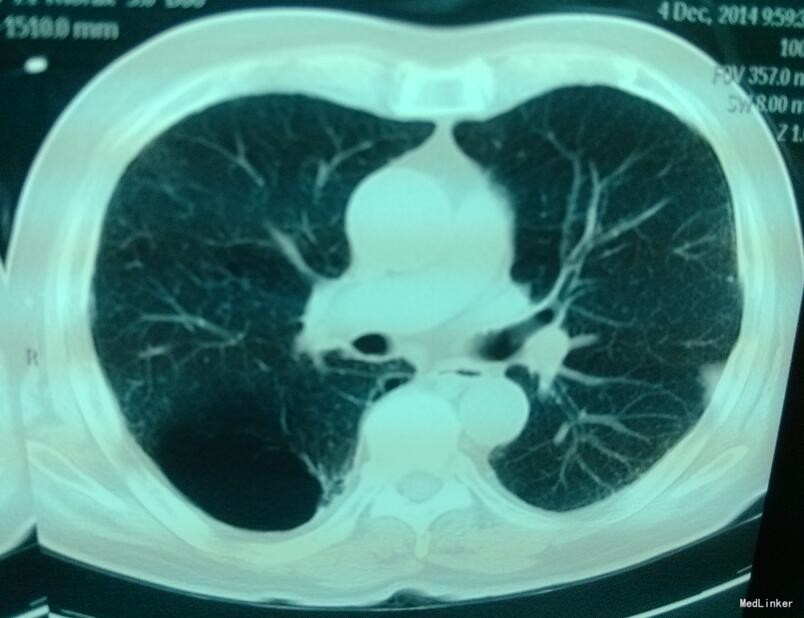

胸部CT提示双肺散在感染灶,右上肺肺大泡,伴胸膜增厚。

诊断为:1、右上肺肺大泡,2、COPD。患者经内科保守治疗后稍好转,遂继续观察。

肺大泡在影像上看比较明显,肺窗上没有血管纹理。平时需要注意些什么呢,如果不手术切除的话会不会平时间发生破裂引起气胸?